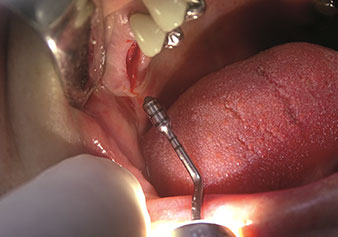

W&H also offers the perfect solution for the internal sinus lift.

Following preparation of the maxillary sinuses with the corresponding instrument set (Fig. 3), the new Z35P instrument (Fig. 4) is used to lift the membrane hydrodynamically. The same instrument set can also be used for piezosurgical preparation of the implant bed in increasing diameters (Figures 3 and 4 included with the kind permission of Dr Mario Kirste, Frankfurt/Oder).

Reduction of morbidity risk